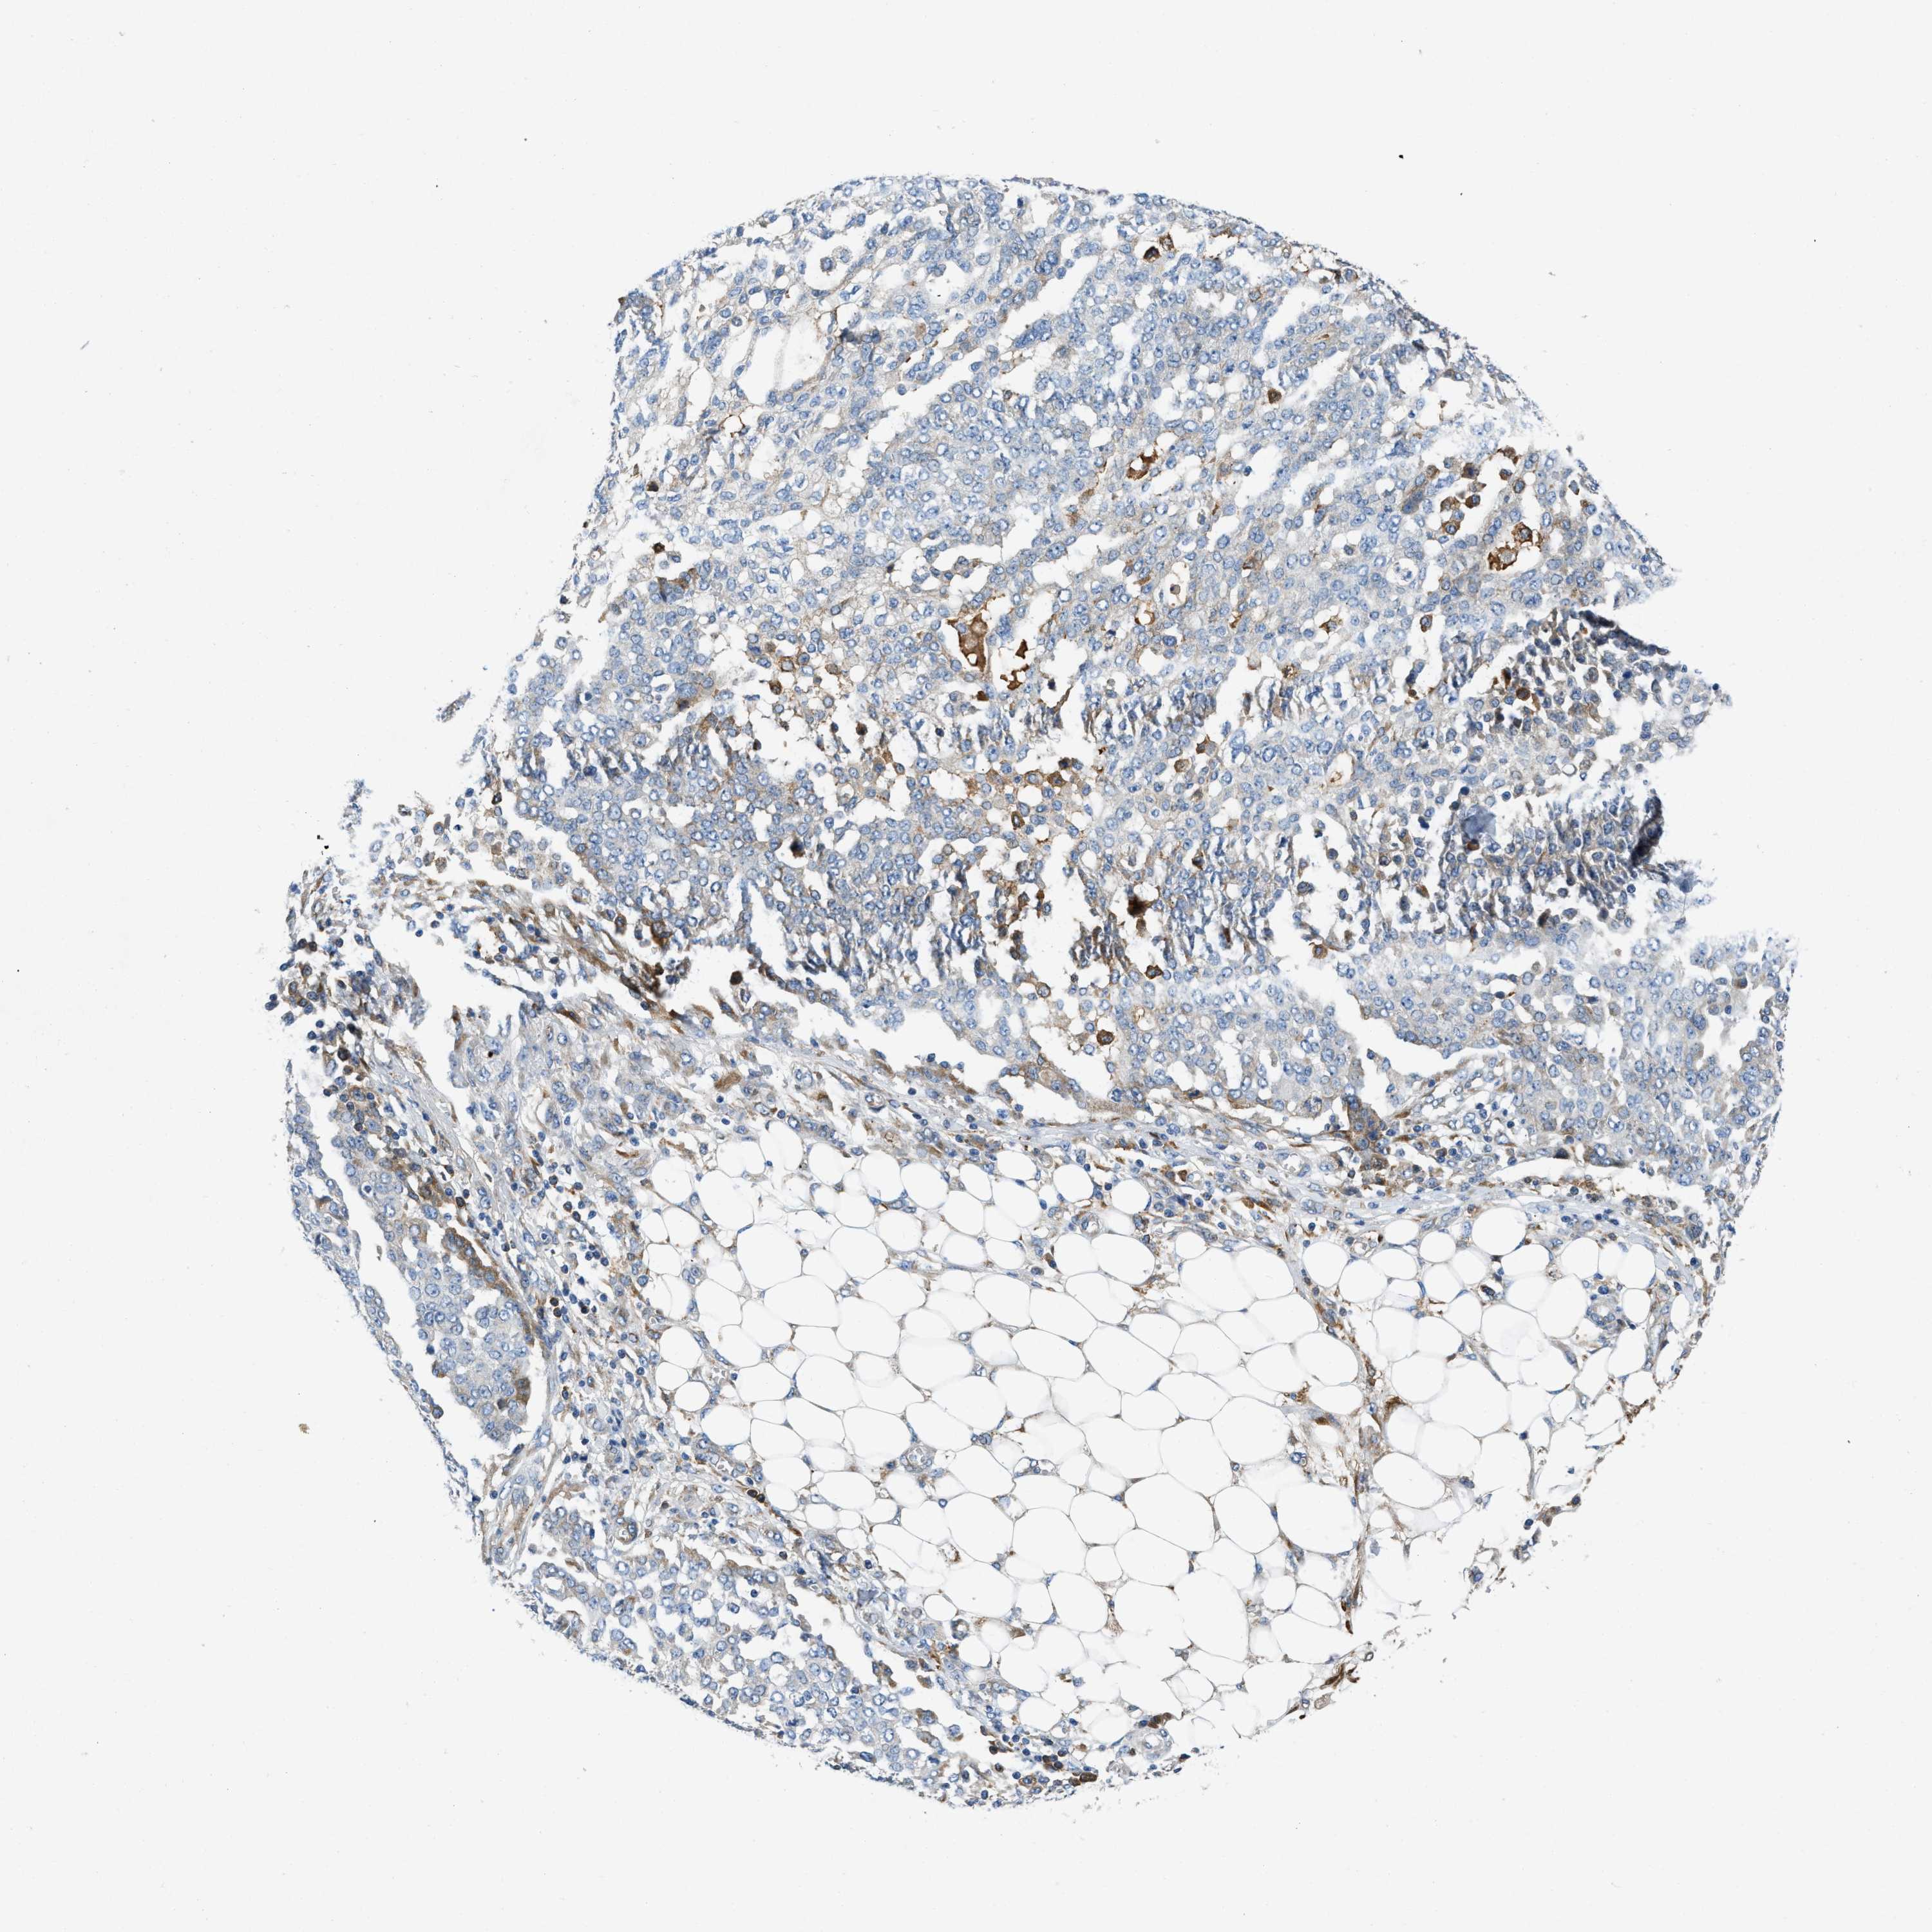

OVARIAN CANCER - Protein expressioni

A mouse-over function shows sample information and annotation data. Click on an image to view it in a full screen mode. Samples can be filtered based on level of antibody staining by selecting one or several of the following categories: high, medium, low and not detected. The assay and annotation is described here.

Note that samples used for immunohistochemistry by the Human Protein Atlas do not correspond to samples in the TCGA dataset.

Antibody stainingi

Antibody staining in the annotated cell types in the current human tissue is reported as not detected, low, medium, or high, based on conventional immunohistochemistry profiling in selected tissues. This score is based on the combination of the staining intensity and fraction of stained cells.

Each image is clickable and will lead to virtual microscopy that enables deeper exploration of all samples and also displays staining intensity scores, fraction scores and subcellular localization as well as patient and tissue information for each sample.

Antibody HPA018284

Staining

High

Medium

Low

Not detected

Intensity

Strong

Moderate

Weak

Negative

Quantity

>75%

75%-25%

<25%

None

Location

Nuclear

Cytoplasmic/membranous

Cytoplasmic/membranous,nuclear

Cystadenocarcinoma, serous, NOS

Carcinoma, endometroid

Cystadenocarcinoma, mucinous, NOS

Carcinoma, NOS